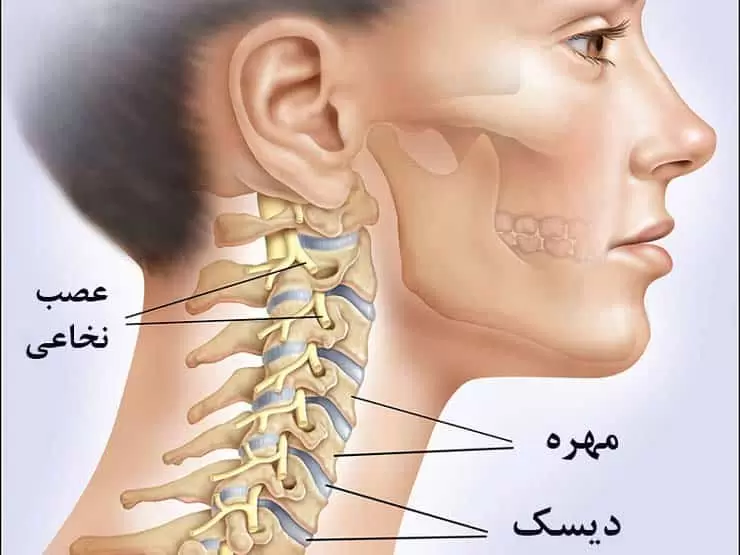

گرفتگی عضلات گردن یکی از اختلالات شایع سیستم عضلانی اسکلتی است که میتواند فعالیتهای روزمره فرد را دچار اختلال کند. این عارضه با علائمی نظیر درد و اسپاسم عضلات گردن، کاهش دامنه حرکتی، سردرد، دردهای تیرکشنده به سمت شانه و بازو و در برخی موارد گزگز یا بیحسی همراه...

دیسک گردن یکی از مشکلات شایع در دنیای امروز است که میتواند کیفیت زندگی فرد را به شدت تحت تاثیر قرار دهد. معمولا دردهای گردن به دلایل مختلفی از جمله آسیب، ضربه، آرتروز، یا مشکلات دژنراتیو دیسکها ایجاد میشود. این دردها ابتدا ممکن است در ناحیه گردن احساس شوند،...